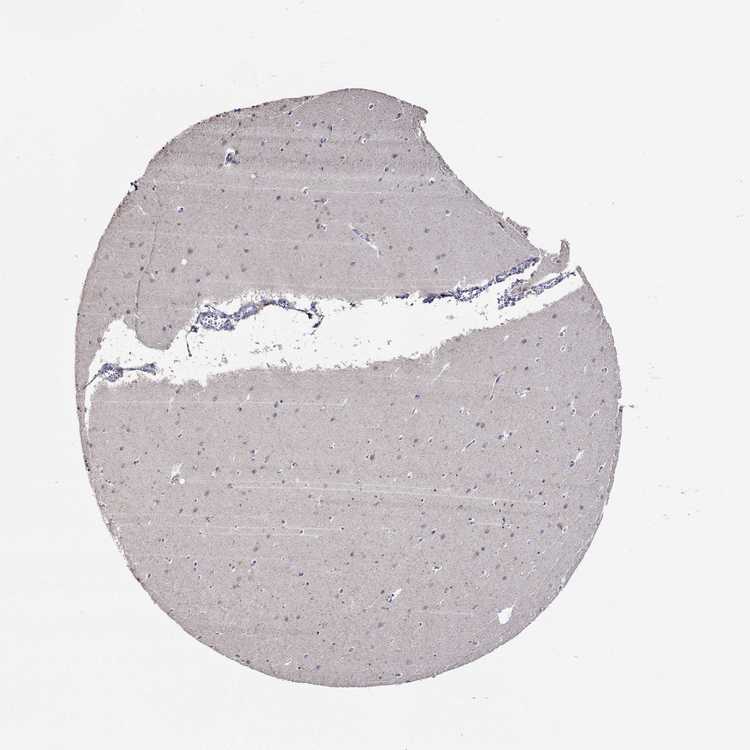

CEREBELLUM - Antibody stainingi

Antibody staining in the annotated cell types in the current human tissue is reported as not detected, low, medium, or high, based on conventional immunohistochemistry profiling in selected tissues. This score is based on the combination of the staining intensity and fraction of stained cells.

Each image is clickable and will lead to virtual microscopy that enables deeper exploration of all samples and also displays staining intensity scores, fraction scores and subcellular localization as well as patient and tissue information for each sample.

Antibody HPA060505Antibody HPA067637

Purkinje cells Not detectedNot detected

Cells in granular layer Not detectedLow

Cells in molecular layer Not detectedNot detected